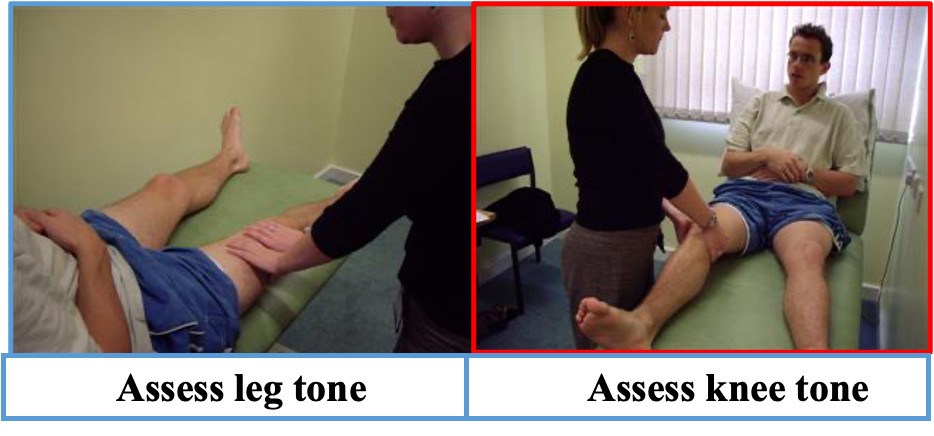

LL MOTOR EXMINATION

Tone As with all examinations, the best method is your own – one with which you are comfortable and familiar. The one explained here takes the following format:

- Tone.

- Power.

- Reflexes.

- Function.

- Sensation.

Power A full motor system examination includes assessment of the legs and the following format:

- Tone.

- Power.

- Reflexes.

- Function.

- Sensation.

Start at the hip asking the patient to abduct, adduct, flex and extend against your hand so you can assess how much force they can overcome.

Do the same for flexion and extension at the knee and ankle as well as the toes.